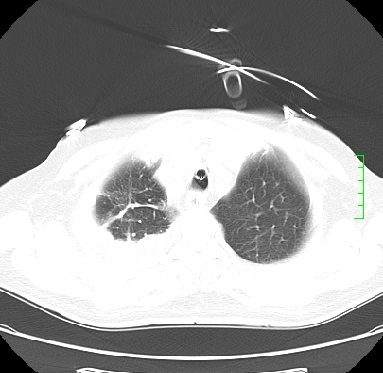

icu病人,几天都没明确诊断。m,76y,咳嗽、咳痰1周,伴气促,右胸痛入院,pe:t38.3c p135 r25 bp135/85。双肺可闻及大量湿罗音,心、腹未见明显异常。诊断:1心衰?2肺部感染?3冠心病?

11号ct

双肺感染性病变,下叶膨胀不全,胸水,左室大。

1)两肺感染性病变(右肺下叶肺脓肿可能)。2)双侧胸腔积液,以右侧为甚。

混合型肺水肿合并感染,肺膨胀不全,胸膜肥厚粘连包裹,同时肺内有陈旧性病灶。注意复查

ards,肺感染性病变,右下叶实变,双侧胸腔积液,右侧为著,叶间胸膜积液,右上肺陈旧性tb纤维灶,左室大。